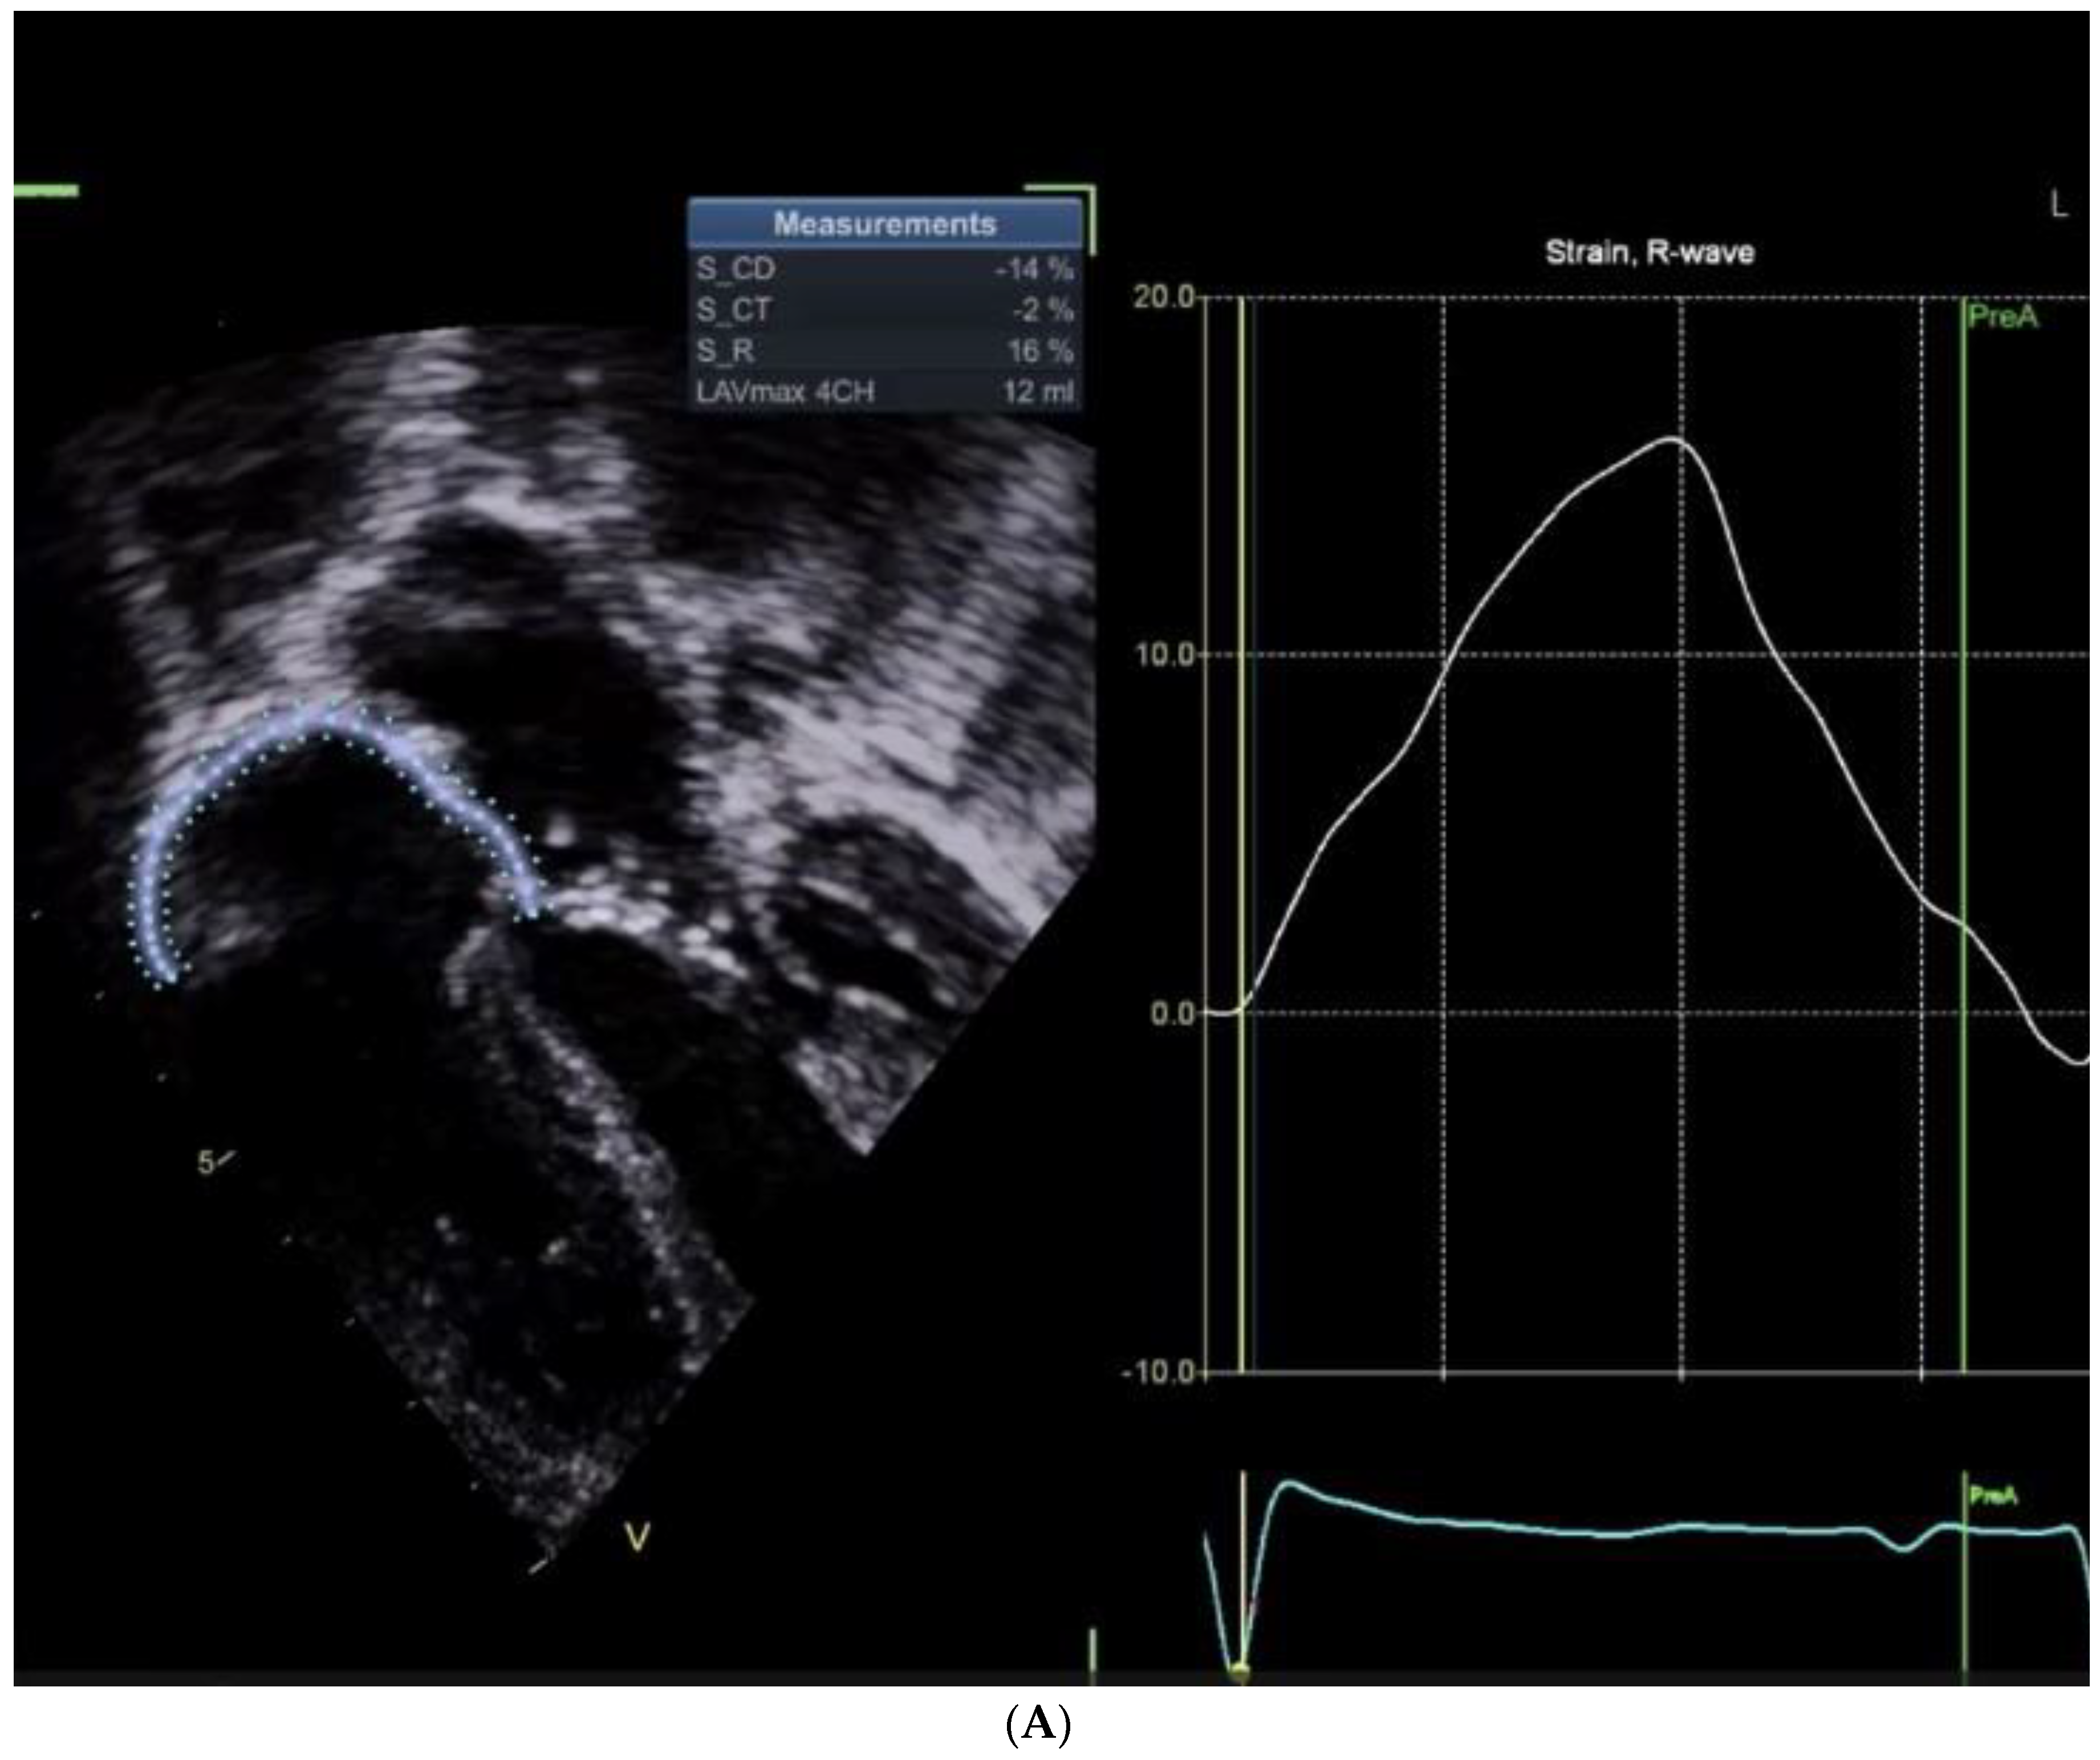

Right Atrial Functions Are Shown in Figure 1A and Figure 1B.

Table 1 Summarizes the Findings of Figure 1 A and B

Despite successful surgical results and myocardial functions, the Right Atrial (RA) conduit function is noticeably reduced, reflecting the lack of passive atrial shortening, and the reservoir function is mildly reduced. Notably, the impaired passive shortening is compensated by an exaggerated atrial kick compared to the patient who has not undergone ASD closure.

Figure 1. A: Right atrial functions assessment in a patient following a non-ASD cardiac surgery (mitral cleft closure). B: Right atrial functions assessment four days following post-ASD closure, presenting a small rim of pericardial effusion developing in the vicinity of the right atrium.

S/P ASD Closure S/P Mitral valve repair Cut-offs

(Absolute values)

Conduit -5 -14 >11%

Reservoir 12 16 >18-22%

Contractile -7 -2 >8-12%